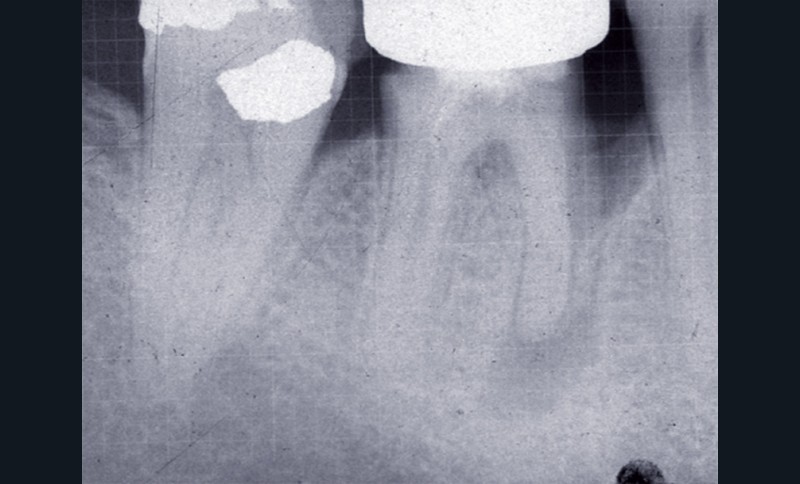

L’examen radiographique met en évidence un traitement endodontique incorrect, une lésion périapicale et une poche parodontale infra-osseuse au niveau de la racine mésiale (fig. 1 et 2).